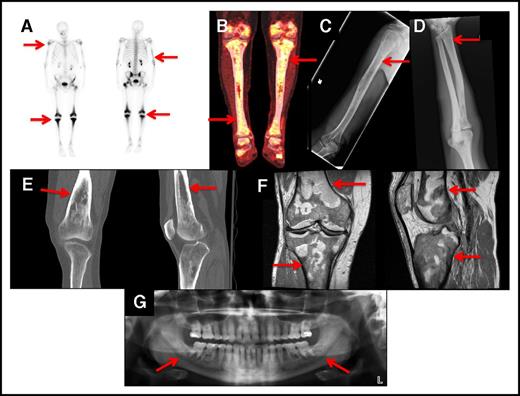

Bone lesions in ECD are described as osteosclerosis or polyostotic sclerosis as evident on scintigraphic studies of long bones.7,8 Bone involvement was present in 95% of cases and involved the appendicular skeleton and occasionally the axial skeleton. Technetium-99 bone scans (Figure 1A) and FDG PET-CT scans (Figure 1B) revealed increased uptake in affected areas. Long bone osteosclerosis was detected on plain radiographs (Figure 1C-D), CT (Figure 1E), and MRI (Figure 1F). Panoramic imaging showed bilateral midroot radiolucencies in the maxilla and mandible (Figure 1G) in 47% of cases (n = 51). For long bones, bilateral involvement was seen in the femur in 88% of patients, tibia in 88%, humeri in 42%, and radii in 42%. In addition, the skull, vertebrae, mandible, pelvis, and ribs occasionally contained lesions, and MRIs of the head showed thickening of the facial bones and maxillary sinuses in 50% of cases. Technetium-99 bone scan was the imaging modality with the highest sensitivity in detecting bone disease when compared with plain film radiographs. Plain radiographs detected osteosclerosis in the radii in 42% of patients (26 out of 60) and in the femur and tibia in 60% (36 out of 60) and 65% (39 out of 60), respectively. In comparison, T-99 bone scans showed increased radiotracer uptake in the radii in 47% of the cases (28 out of 60) and in the femur and tibia in 88% (53 out of 60). There was no evidence of bone disease in 5% of the cases. In our series, 82% of patients had received therapy prior to our evaluations. Approximately half of the affected individuals described deep, dull bone pain, especially in the knees.

Bone lesions in ECD. The red arrows show: (A) Whole-body bone scan with technetium-99 showing avid uptake in the knees and left hip of an ECD patient. Less intense uptake occurs bilaterally in the humeri and distal tibias. (B) FDG PET-CT scan showing increased FDG uptake in the knees and proximal and distal tibias. (C) Bone radiograph showing cortical osteosclerosis in the right humeri. (D) Bone radiograph showing cortical osteosclerosis in the distal right radius. (E) CT scan of the right knee of an ECD patient showing cortical osteosclerosis and mottled appearance of the bone. (F) MRI scan of the right knee of an ECD patient showing serpiginous areas of T1 signal hypointensity, indicative of osteosclerosis. (G) Panoramic radiograph showing bilateral osteosclerosis of the mandible and maxillary sinus disease.